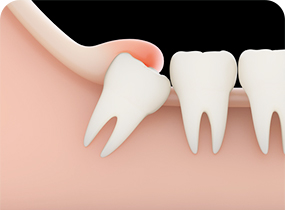

CASE 01

사랑니로 인해 잇몸이 붓고

염증이 생긴 경우 -